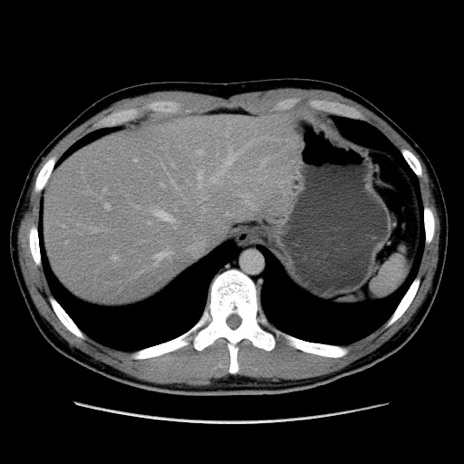

冠状断像

【症例】20歳代 男性

【主訴】心窩部痛

【現病歴】今朝より上腹部痛あり。一旦軽快していたが再度出現したため救急要請。昨日夕に白身の魚を含む刺身を食べた。

【身体所見】BP 136/89mmHg、HR 74/min、BT 37.0℃、腹部:膨満、軟、心窩部に圧痛あり。反跳痛なし、筋性防御なし、腸雑音やや亢進あり。

【データ】WBC 17700、CRP 0.48